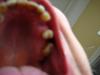

nisa Опубликовано 28 апреля, 2008 Автор Поделиться Опубликовано 28 апреля, 2008 (изменено) Не надо этого делать! Жалко. А чтобы ответить на вопрос "что надо делать" нам нужны, как всегда, снимки.Вот как это выглядит 5 зуб недавно удалили.А бабочка, под нее ничего не обтачивают? И почему не функционально? Изменено 28 апреля, 2008 пользователем nisa Ссылка на комментарий

Dr. Stom Опубликовано 28 апреля, 2008 Поделиться Опубликовано 28 апреля, 2008 (изменено) Вот как это выглядит 5 зуб недавно удалили.снимок интерестный, но мне кажется что Док говорил о ренгеновском снимке ЗЫ: а на вашем фото помойму у Вас отсутствуют 24 и 26 зубы или меня глючит... Изменено 28 апреля, 2008 пользователем Dr. Stom Ссылка на комментарий

nisa Опубликовано 28 апреля, 2008 Автор Поделиться Опубликовано 28 апреля, 2008 снимок интерестный, но мне кажется что Док говорил о ренгеновском снимке ЗЫ: а на вашем фото помойму у Вас отсутствуют 24 и 26 зубы или меня глючит...Ренгеновского снимка не делал. А этот сделал для того чтобы было понятно о чем говорю, я не специалист, поэтому могу сделать ошибку в нумерации. Зуб мудрости у меня не вырос, да похоже я ошибся в подсчетах, отсутствуют 6 и 4, извините. Ссылка на комментарий